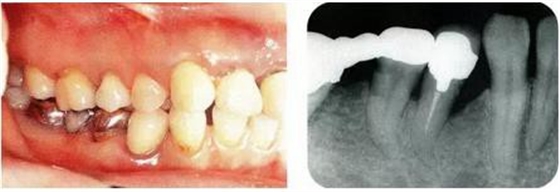

圖17-3▲拔牙的同時做骨外科處理,讓殘留的骨可以盡量平坦化。為了獲得頰側(cè)的附著齦,采用了游離齦瓣的處理。

圖17-4(左),5 (右)▲術(shù)后9年的口腔內(nèi)照片和X線片,牙槽嵴平坦化,牙周探診數(shù)值很小。